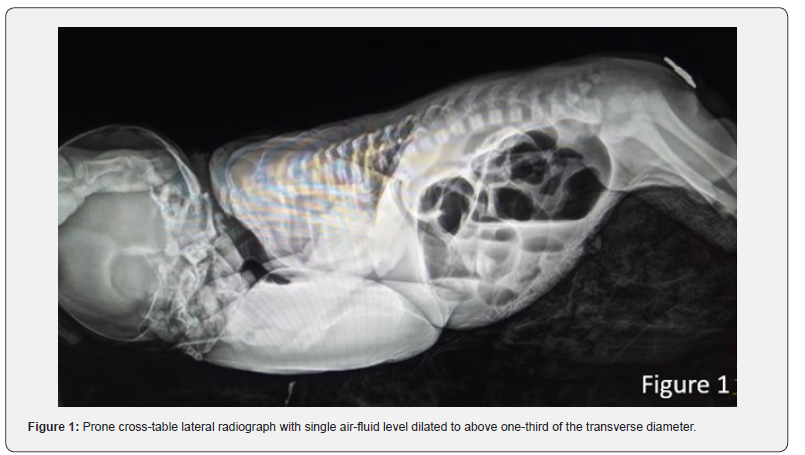

Initial diagnostic workup included a cross-table lateral abdominal X-ray (Figure 1), performed with the infant in the prone position to assess air distribution. The radiograph revealed a high anorectal malformation, characterized by a large, solitary bowel loop occupying the central abdomen, with a single air-fluid level dilated to more than one-third of the transverse abdominal diameter. This finding raised suspicion of congenital pouch colon (CPC), as the extent of dilatation exceeded that typically seen in classical ARM [6]. No free intraperitoneal air or calcifications were noted, ruling out perforation or meconium peritonitis. Following resuscitation with intravenous fluids, nasogastric decompression, and broad-spectrum antibiotics (ampicillin and gentamicin), the neonate was prepared for exploratory laparotomy. Intraoperative exploration confirmed the radiographic suspicion: the descending colon abruptly terminated in a dilated, thick-walled distal pouch, devoid of haustra or taeniae coli, with no fistulous connection to the urinary tract or other structures (Figure 2). The pouch was located distal to a short segment of normal-appearing colon, consistent with type 4 CPC per the Narsimha Rao classification [3]. The bladder and ureters appeared anatomically normal, and no additional intra-abdominal anomalies were identified. The diagnosis of CPC was thus established based on the triad of a shortened colon, pouch-like dilatation, and association with ARM, as delineated by Gupta & Sharma [1] with the absence of a fistula marking this as a rare variant.